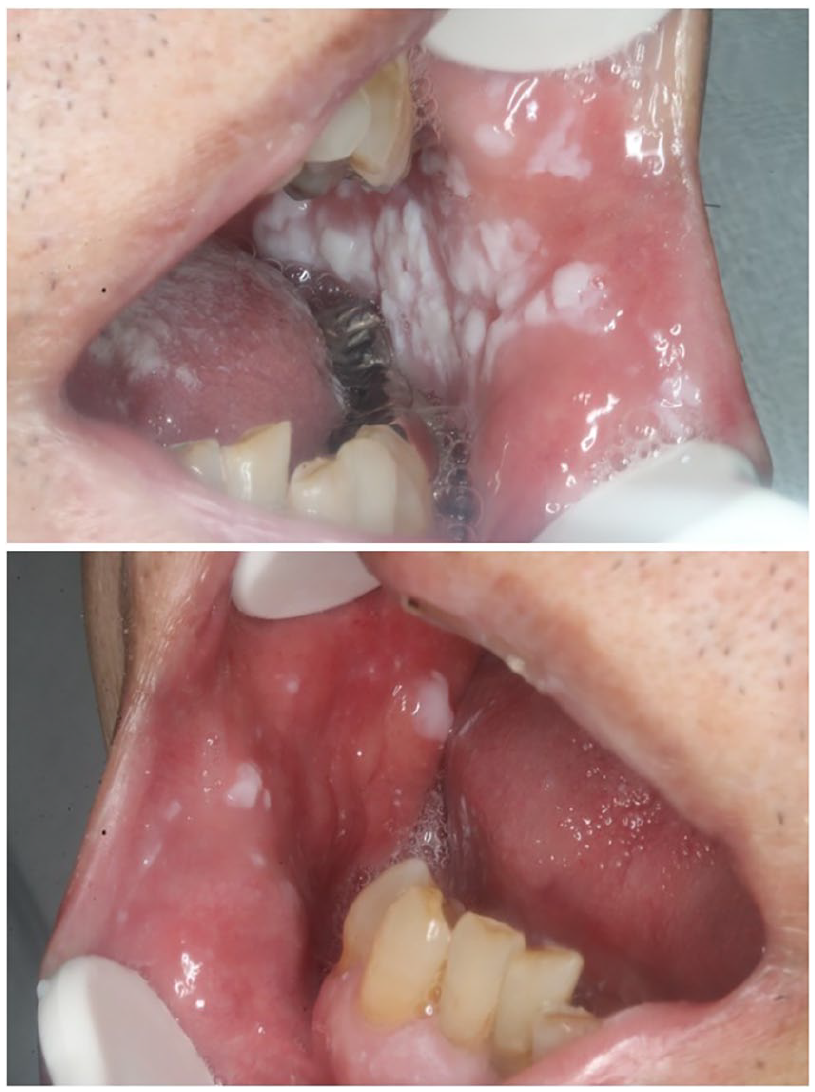

The patient was a 75-year-old man patient with a medical history of atrial fibrillation taking warfarin. Fever and impaired consciousness were noted in mid-March 2020, and the patient was transferred to our hospital as an emergency. COVID-19 pneumonia was suspected due to a history of close contact with spouse who had COVID-19, increased fever and respiratory rate, decreased permeability of the right whole lung field on chest X-ray, and accumulation of pleural effusion. He was urgently admitted via the emergency department. A positive polymerase chain reaction test result for COVID-19 was confirmed, and a definitive diagnosis of COVID-19 pneumonia was made. After admission, an oral combination of lopinavir/ritonavir (800 mg/200 mg/ day, twice daily) was administered, and ciclesonide (800 µg/day, twice daily) was inhaled for 7 days. On the 7th day of hospitalization, aspiration pneumonia was observed. On the 14th day of hospitalization, white plaque began to appear in the oral cavity. At the first visit to our department on the 14th day, white plaque was found on both buccal mucosa and the back of the tongue, but there was no oral pain or dysgeusia.

Oral candidiasis in a patient with COVID-19 14 days after admission. White plaque on the tongue and buccal mucosa is visible.

Oral candidiasis in a patient with COVID-19 (35 days after admission) after oral treatment. The white plaque on the oral mucosa is no longer visible.